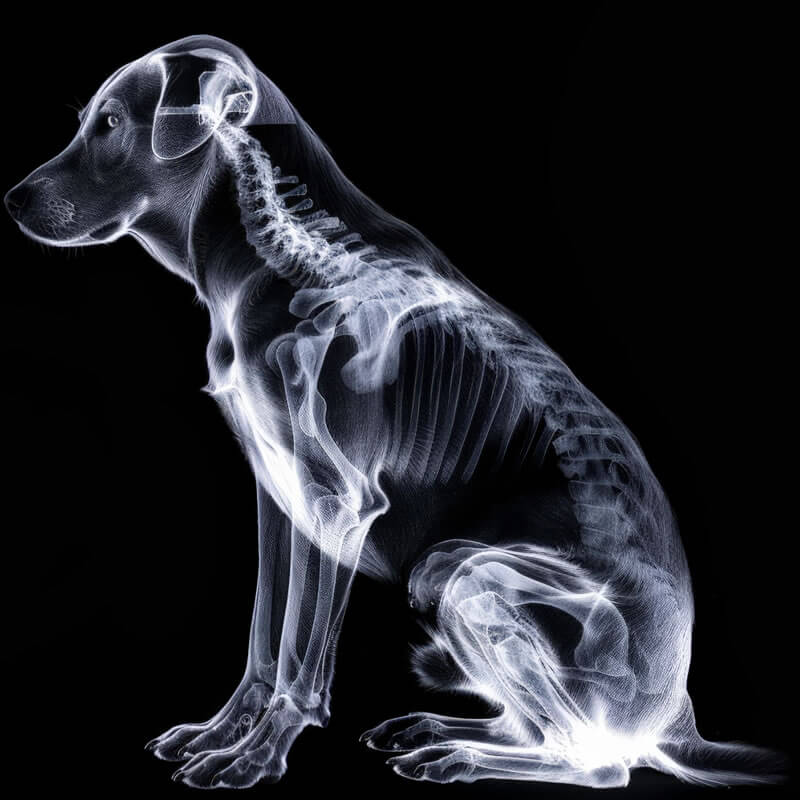

Ortopedia Especializada

Tratamento clínico e cirúrgico com equipamentos de alta tecnologia para problemas ósseos e articulares.